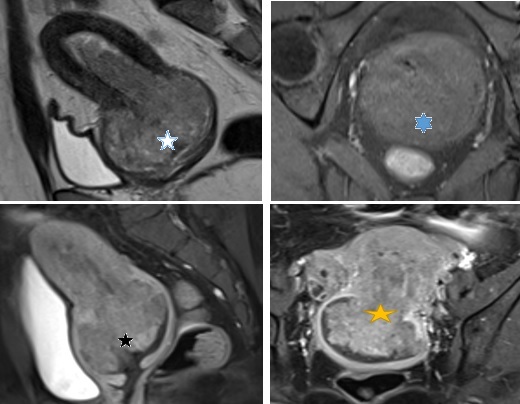

Kết quả MRI: Từ buồng nội mạc lan tới âm đạo có khối choán chỗ kích thước # 68 x 86 x 72 mm (trước sau- cao -ngang), tín hiệu trung gian trên T2W, thấp trên T1W, hạn chế khuếch tán, bờ ngoài u không đều, đa thuỳ, u xâm lấn không thấy cổ tử cung. U có cuống xuất phát từ vùng đáy tử cung. Sau tiêm Gd, u bắt thuốc tương phản mạnh không đồng nhất. Dọc vách chậu hai bên có vài hạch hình tròn kích thước # 9 x 15 mm, bờ ngoài không đều, bắt thuốc tương phản kém. Rải rác phúc mạc vùng chậu có vài nốt bất thường tín hiệu kích thước </= 17 x 22 x 15 mm, bờ đa cung, hạn chế khuếch tán, bắt thuốc tương phản không đồng nhất.Vùng phía sau gan ngay hạ phân thuỳ VIII có nốt bất thường tín hiệu kích thước # 27 x 20 mm, tín hiệu trung gian trên T2, thấp trên T1, bắt thuốc tương phản kém sau tiêm, khối này ấn lãm bờ gan

Kết luận: Hình ảnh gợi ý sarcoma cơ tử cung xâm lấn cổ tử cung. Chẩn đoán phân biệt: Ung thư nội mạc tử cung giai đoạn IVB (FIGO), hạch vách chậu hai bên dạng hạch di căn, nốt phúc mạc vùng chậu nốt ở sau gan phải ấn lõm bờ gan nghĩ mô u reo rắc

Hình 4: Hình trên trái T2W sagital thấy khối từ lòng tử cung lan xuống cổ tử cung, xâm lấn cơ vùng cổ tử cung. tổn thương có tín hiệu cao nhẹ không đồng nhất trên T2W (ngôi sao trắng). Hình trên phải, T1 FS trên măt cắt ngang thấy tổn thương tín hiệu giống cơ vùng cổ tử cung, không rõ ranh giới giữa tổn thương và cơ vùng cổ tử cung (ngôi sao xanh) . Hình dưới bên trái: sagital T1 FS sau tiêm Gd, tổn thương bắt thuốc tương phản mạnh không đồng nhất (ngôi sao đen). Hinh dưới phải: T1 FS coronal sau tiêm tổn thương bắt thuốc tương phản mạnh không đồng nhất ( ngôi sao vàng)